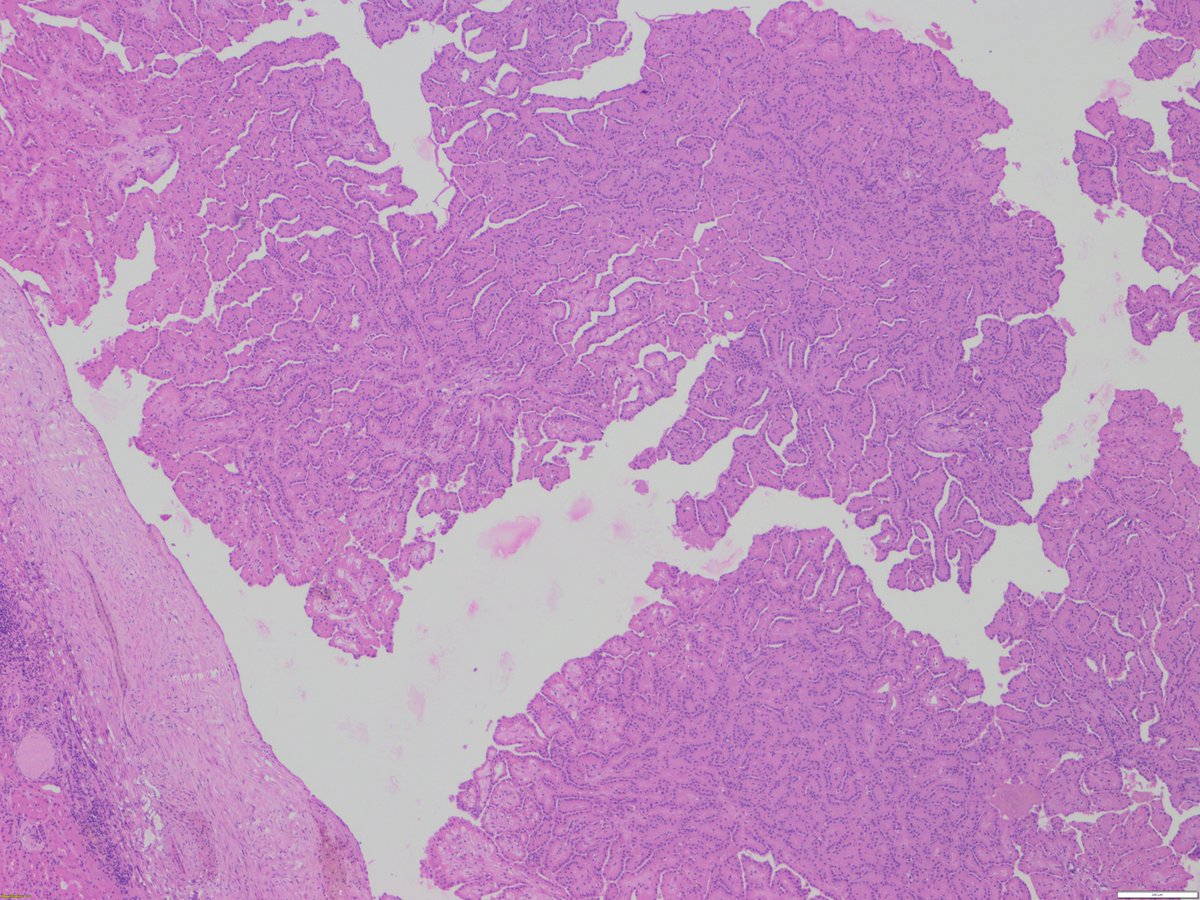

May is #bladdercancerawarenessmonth - important to recognize lesions which mimic #bladdercancer Nephrogenic metaplasia/adenoma: - various architectures (papillary, tubular/glandular, vascular-like...) - cuboidal to hobnail nuclear features - prominence of basement membrane